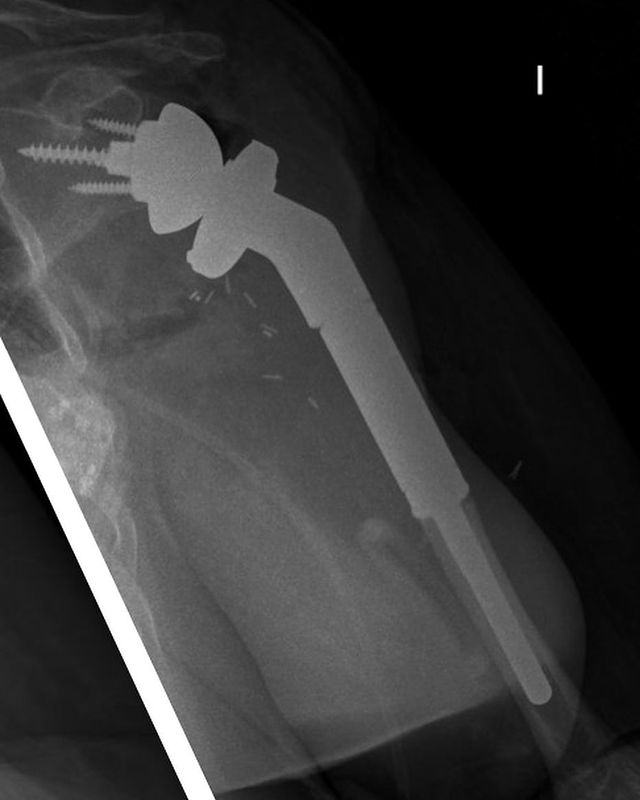

Condrosarcoma en húmero

Hoy me gustaría compartir el caso de una mujer de 72 años con un condrosarcoma G3 de humero izquierdo (imágenes 1,2),  a quien hace 1 año se le realizó una resección (imagen 3) y reconstrucción con la megaprótesis invertida Comprehensive SRS cementada de Zimmer Biomet. (imagen 4) Radiografía de control (5). A los 6 meses presenta un aflojamiento aséptico (imagen 6). Retiramos el componente humeral (imagen 7) y reconstruimos con un ALOINJERTO TELESCOPICO PRESSFIT (imagen 8) y un nuevo componente humeral mas corto (imagen 9) Radiografías de la reconstrucción AloProtésica (imagen 10)

Para poder ayudar a los pacientes con sarcomas debemos tener múltiples opciones reconstructivas, ya sea para el procedimiento inicial, como para las complicaciones que puedan surgir